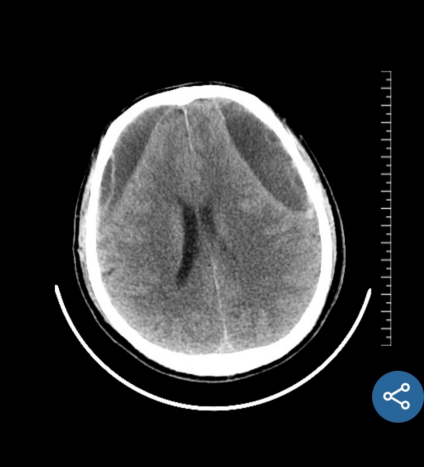

近期,我科完成了一例慢性硬膜下血肿手术。该患者男性,63岁,是因为“摔伤头部半年,记忆力下降,思维迟钝大约20天” 在当地医院就诊,行颅脑CT提示双侧额颞顶部慢性硬膜下血肿,脑疝,CT片可见慢性血肿有很多分隔。当地医院医生建议患者分二次行双侧开颅手术,清除硬膜下血肿,创伤很大,手术后需要住ICU,而且住院时间很长,费用高。患者家属犹豫不决,担心手术风险,于是带着CT片到我科门诊咨询。门诊孟主任阅片后告知家属,我科可以通过神经内镜微创手术治疗慢性硬膜下血肿,可以一次手术,手术创伤小,风险低,费用少,住院时间短,大约10天左右就可以出院,而且手术后不需要住ICU,于是家属当天下午就驱车带患者来我科住院。管床医生涂医生仅用一天时间就完成全部术前检查,第二天就安排了手术。手术中通过神经内镜观察到慢性硬膜下血肿有很多的分隔及纤维组织,与可自行流出的液态慢性血肿相比,该患者需通过吸引器反复仔细吸除血肿分隔及纤维组织,同时反复盐水、双氧水冲洗,避免血肿残留及复发。手术过程很顺利,术后患者清醒,无任何神经功能障碍及并发症,手术后10天患者治愈出院,在后期随访观察中,未见慢性血肿复发。

术前当地医院CT